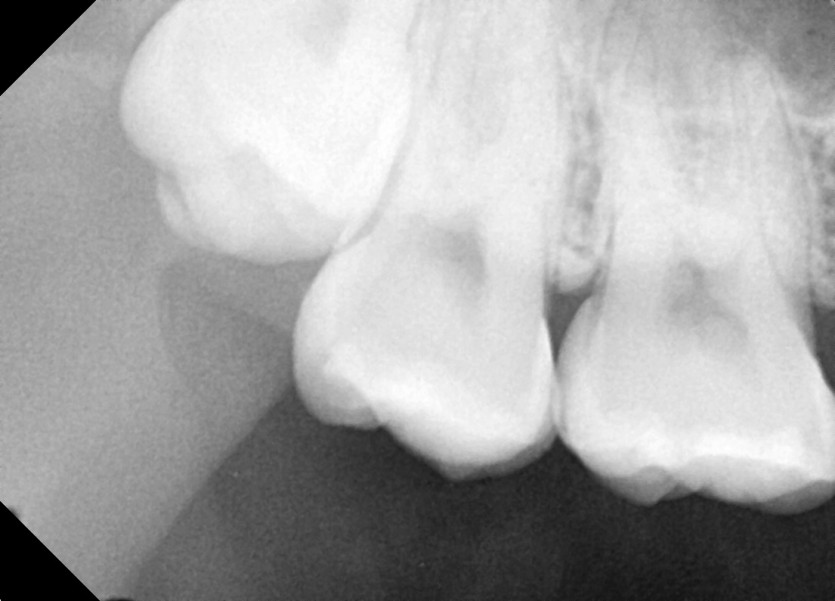

#18,48 사랑니 발치

구강외과 전문의가 당일발치했습니다.